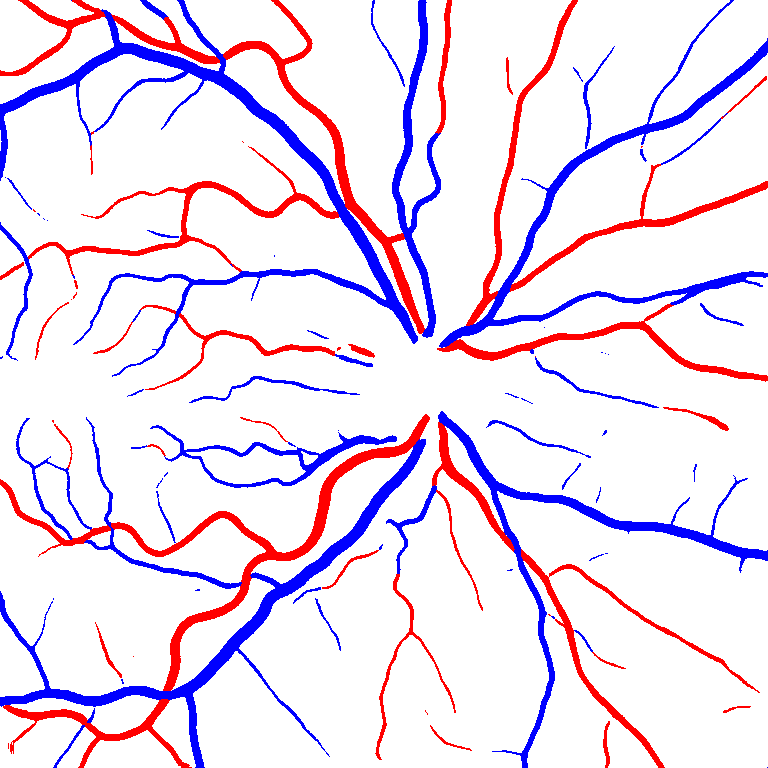

As reported in Table IV, we compared the SegRAVIR model against competing deep learning-based segmentation approaches on the RAVIR dataset. Evidently, SegRAVIR outperforms these methods as judged by all metrics for artery and vein classes with a healthy margin. In terms of Dice score, SegRAVIR outperforms CE-NET, IterNet and AG-Net by , and for artery segmentation and by , and for vein segmentation, respectively. Fig. 4 presents a qualitative comparison of the semantic segmentation outputs of SegRAVIR, CE-Net, and U-Net. Specifically, SegRAVIR yields more accurate vessel topology (i.e., thickness and orientation) segmentation with higher pixel-wise classification accuracy.

(a) (b) (c) (d) (e) (f)